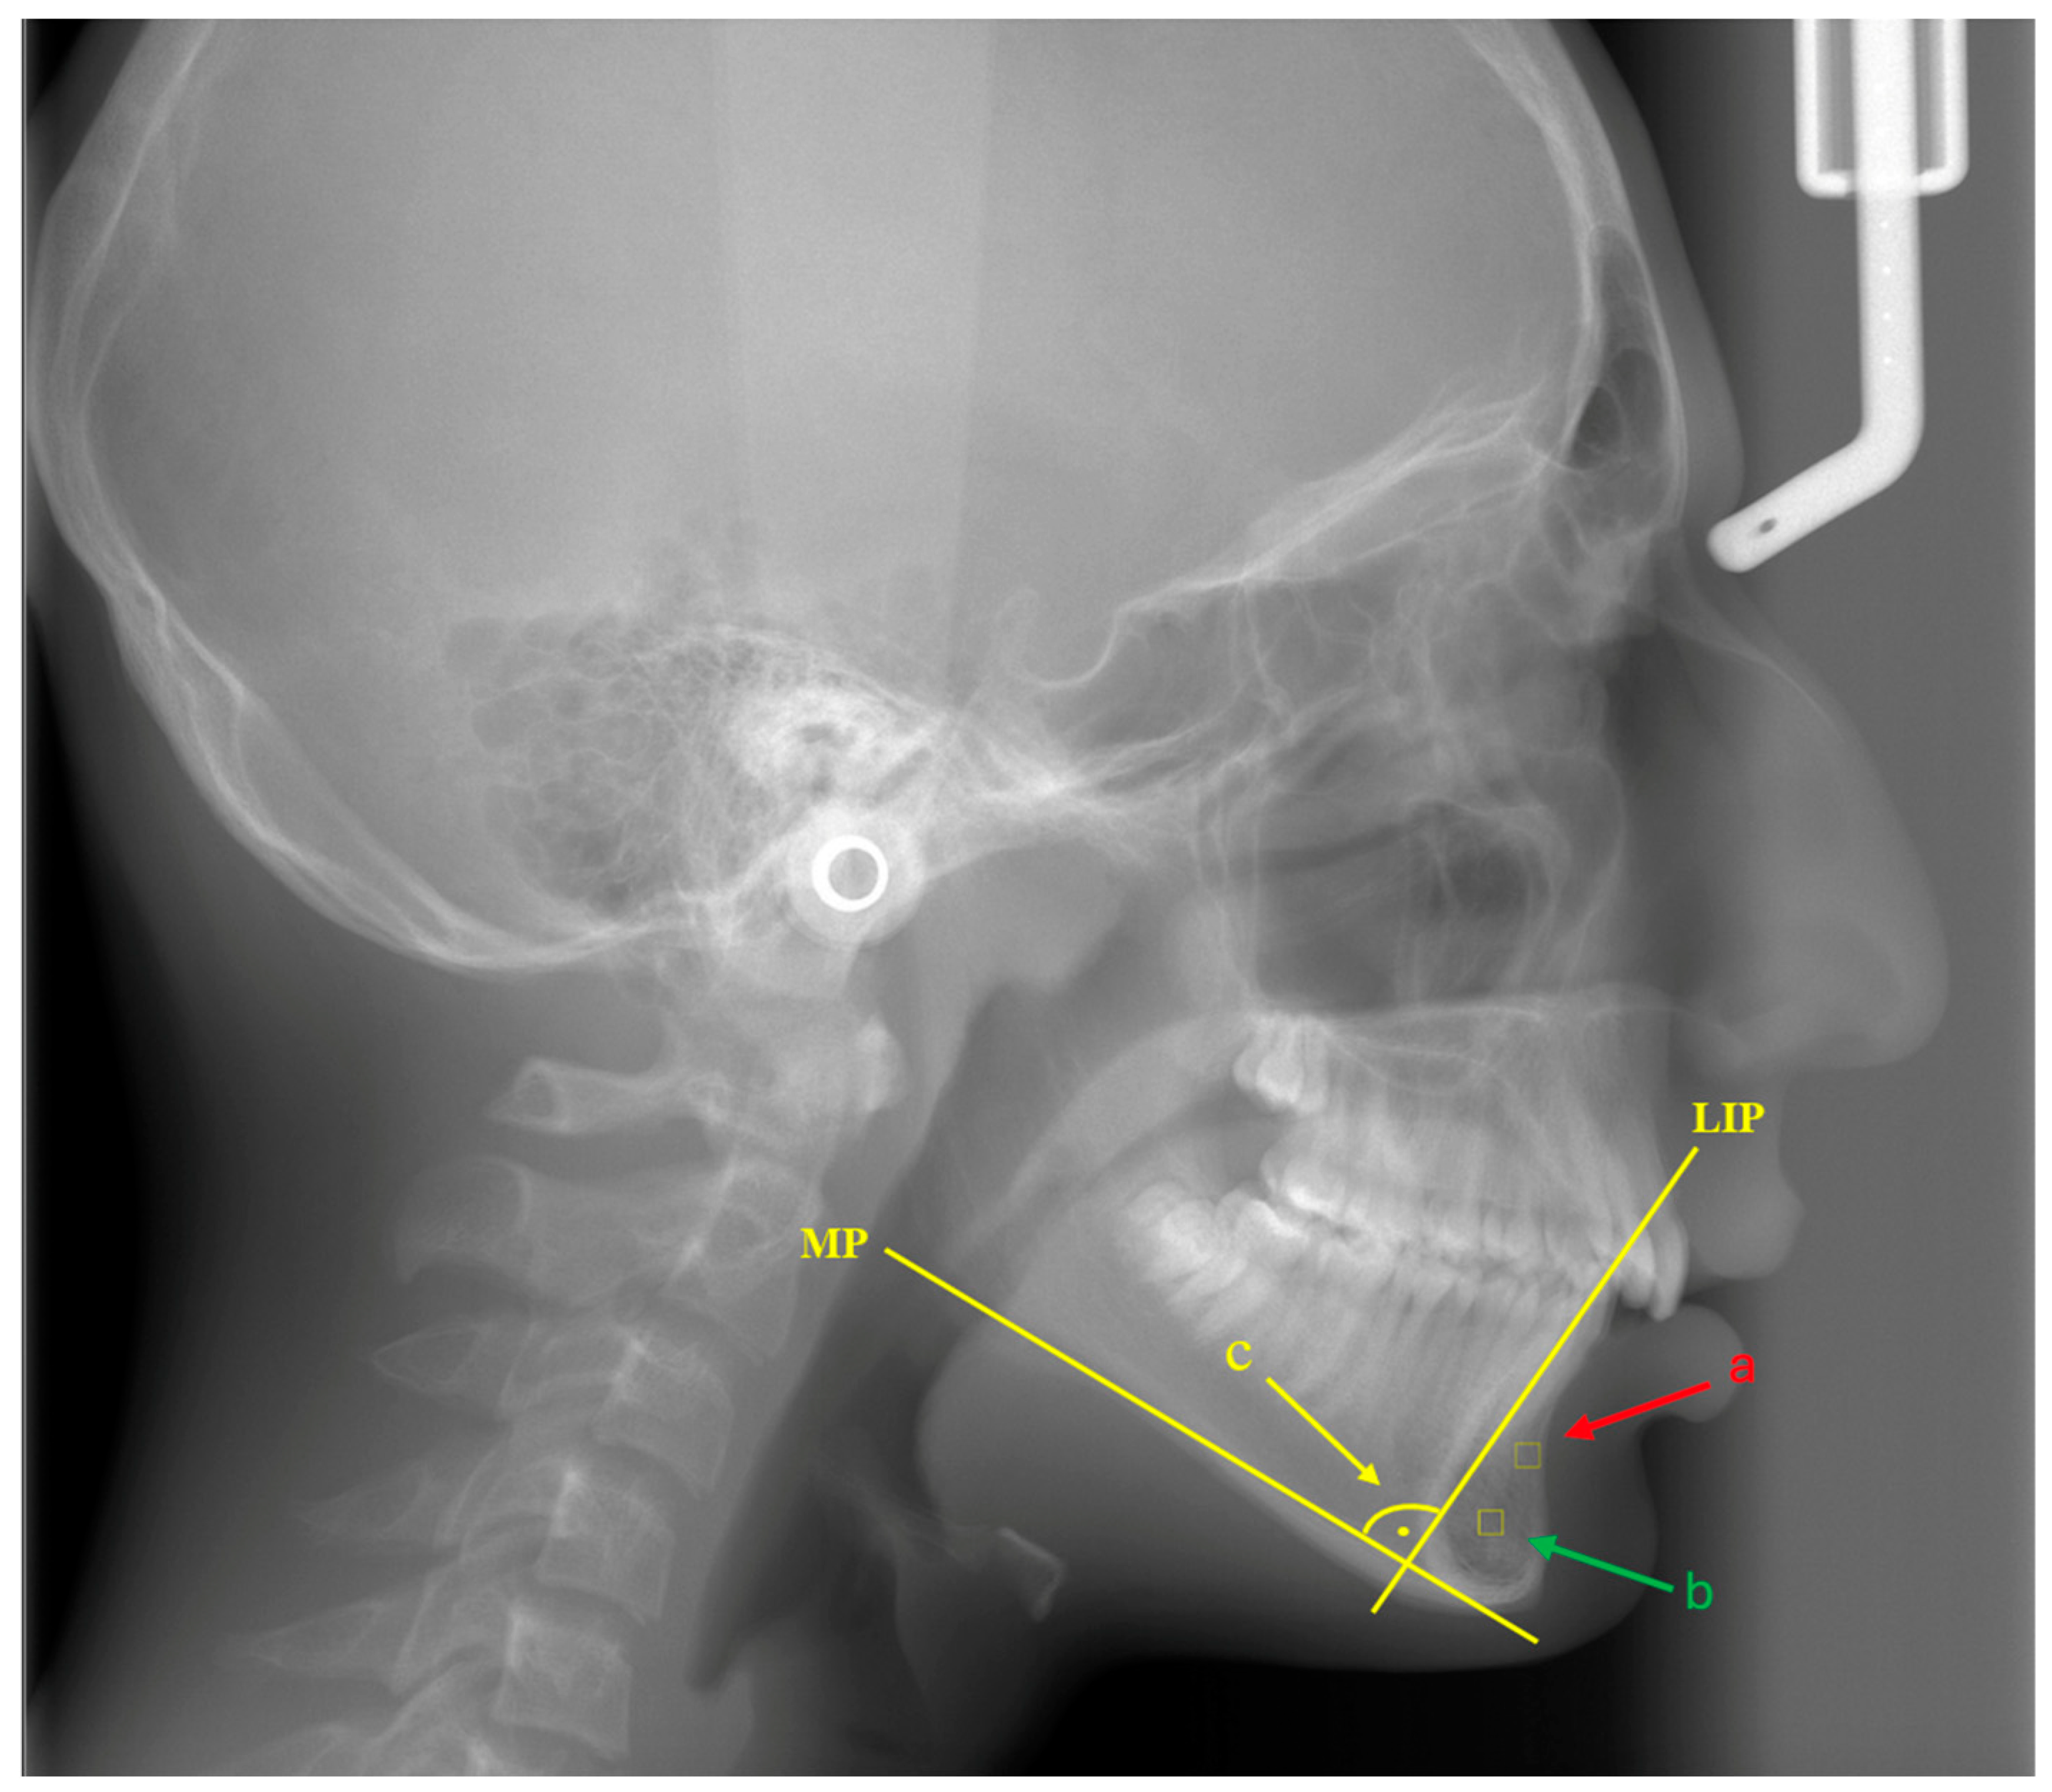

2.4. Interventions and Cephalometric Measurements